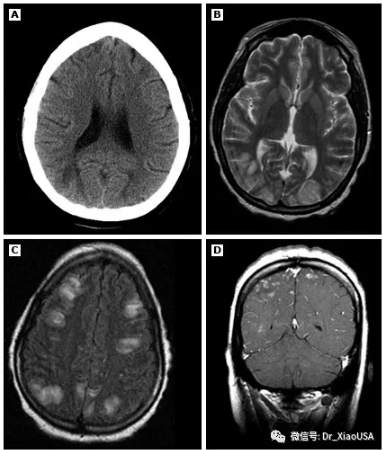

Question 问题:The diagnosis of hypertensive encephalopathy in the ED usually relies on the exclusion of alternative causes of altered mentation. What level of Blood Pressure is required to develop hypertensive encephalopathy?

在急诊科诊断高血压性脑病通常依赖于排除导致神智改变的其他原因。

那么,多高的血压才能出现高血压脑病?